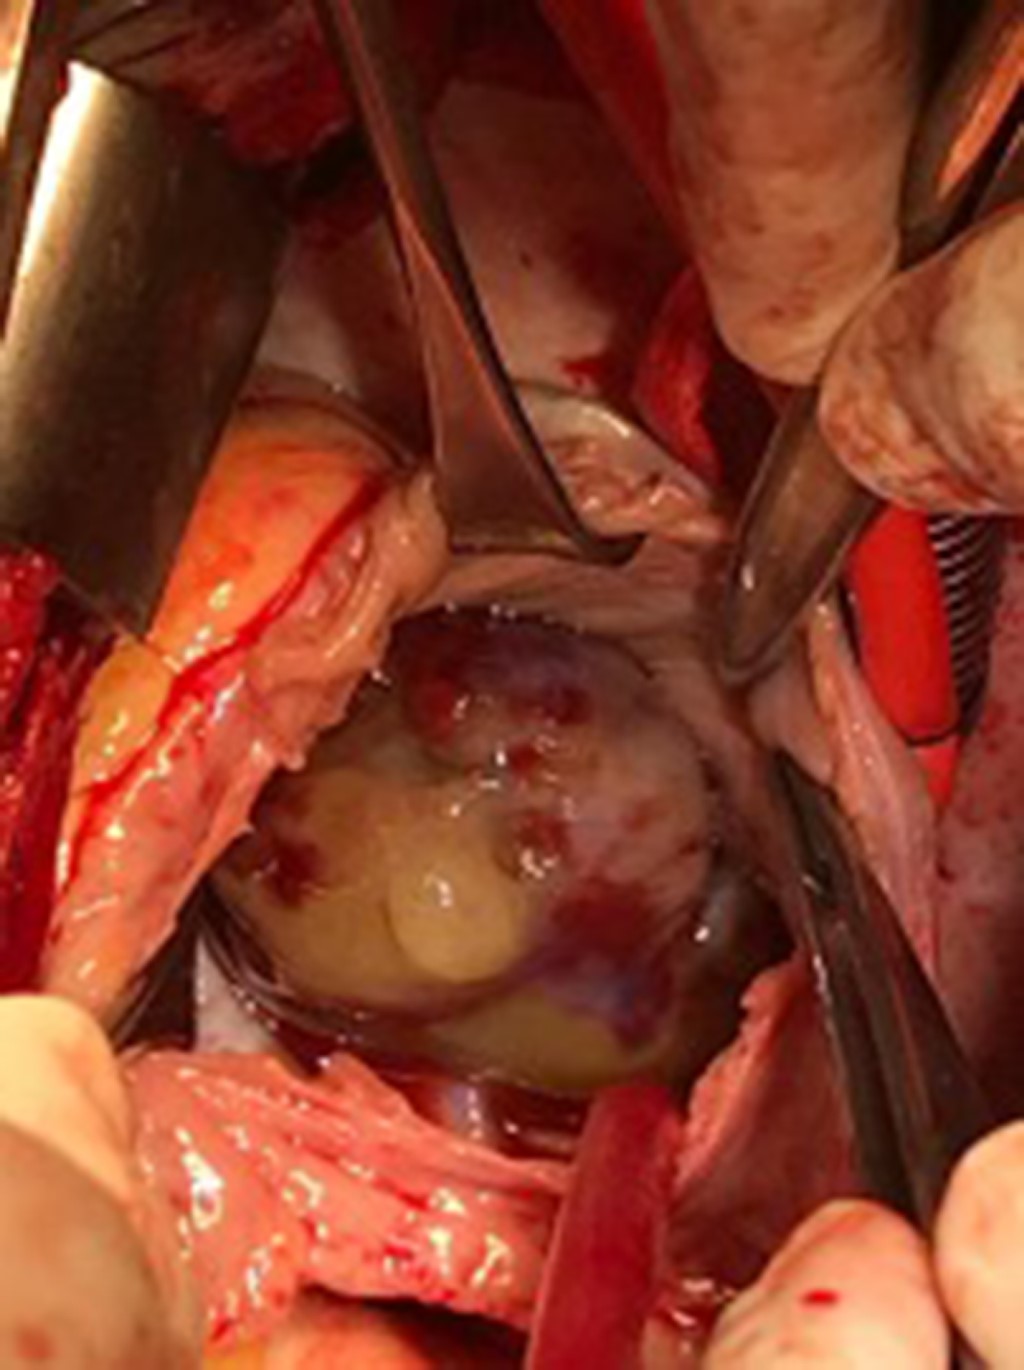

Introducción: los mixomas cardiacos son las neoplasias primarias más frecuentes del corazón. La ubicación más común es la aurícula izquierda (75%), seguido de la aurícula derecha (15-18%) y ventrículo izquierdo. Pueden presentarse con la tríada de síntomas obstructivos, embólicos y constitucionales. Caso 1: varón de 59 años en seguimiento por linfoma cutáneo no Hodgkin de linfocitos T, que padecía disnea progresiva y presentaba una masa localizada en la aurícula derecha. Se realizó resección del tumor y reemplazo de la válvula mitral debido a insuficiencia mitral severa. La histopatología confirmó el diagnóstico de mixoma. Caso 2: mujer de 61 años que consulta por trombosis en vena basílica, cefálica y yugular derecha. Un ecocardiograma mostró una masa cardiaca de 80 × 40 mm en la aurícula derecha. En el informe histopatológico se informó un mixoma cardiaco con el diámetro mayor de 7.5 cm. Fue dada de alta nueve días después de la cirugía. Conclusión: podría haber una presentación inusual de mixoma auricular que ocurra simultáneamente con una neoplasia de diferente linaje. Debe sospecharse mixoma auricular, incluso en ubicaciones inusuales e independientemente de la enfermedad neoplásica concomitante. Los fenómenos embólicos, como la primera presentación, pueden inducir a error; aunque algunos parámetros y puntuaciones pueden ser predictores útiles.

Figura 3